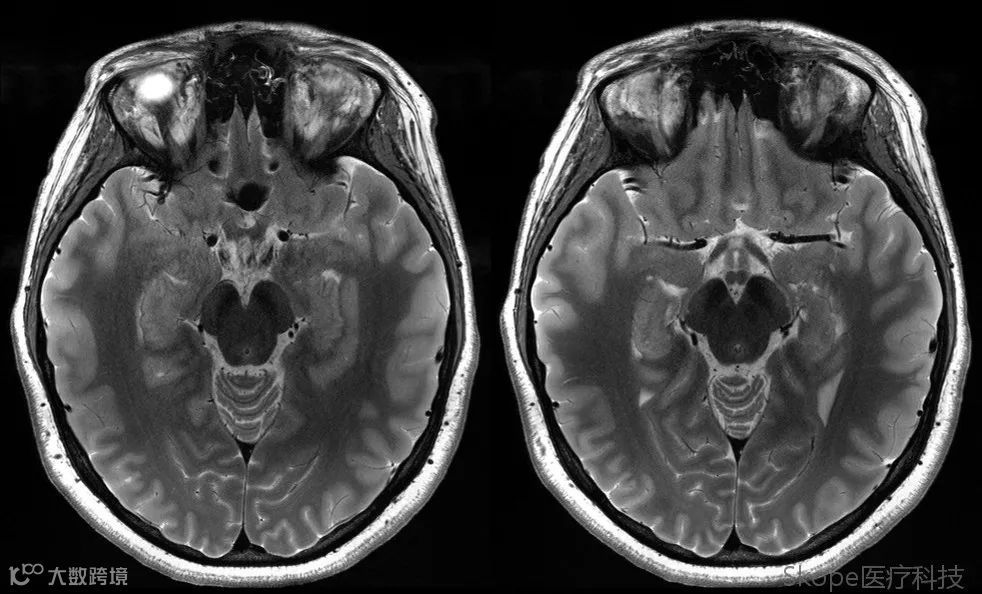

Axial T2 Turbo Spin Echo

左右颞叶信号均匀性良好,且深部脑结构具有良好的信噪比,三叉神经清晰可见。

Right brain hemisphere

Left brain hemisphere

Axial T2 TSE